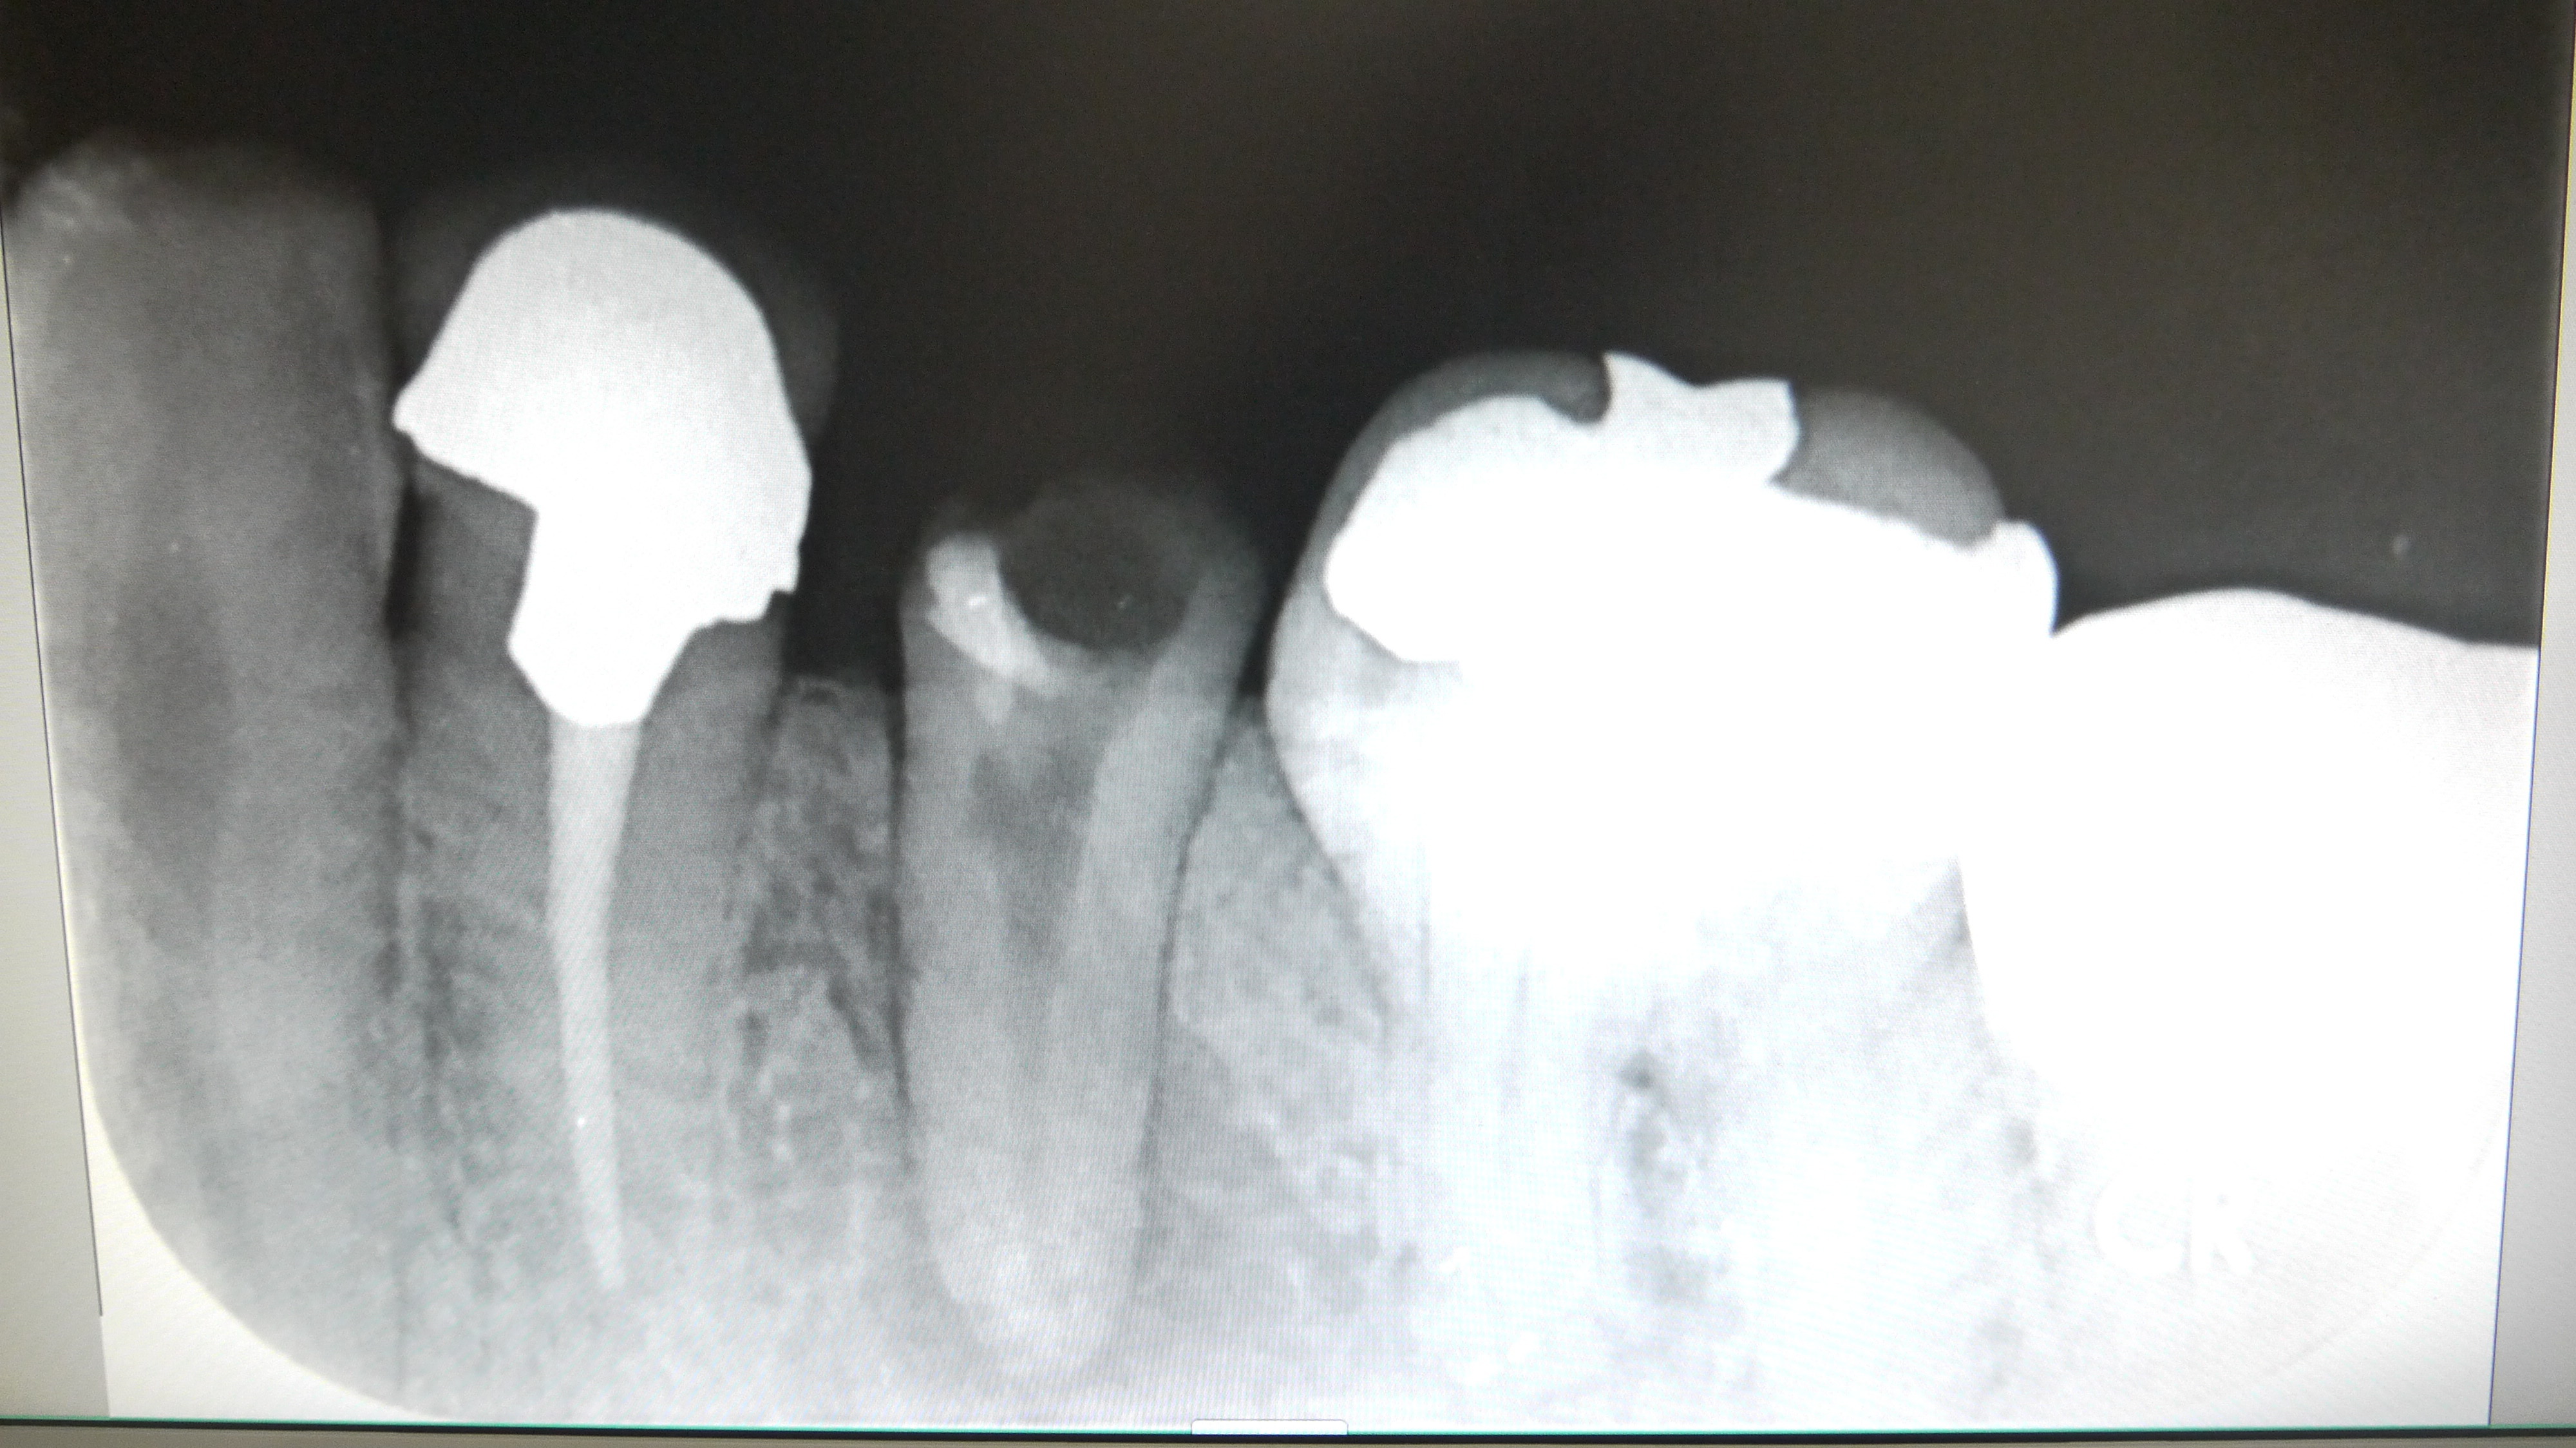

根管の中に薬(ガッタパーチャとシーラー)をつめていきます。(根管処置)

この際、根の長さぴったりまで加圧しながら薬を詰めていくことが

腫れの再発を防ぐために最も重要です。